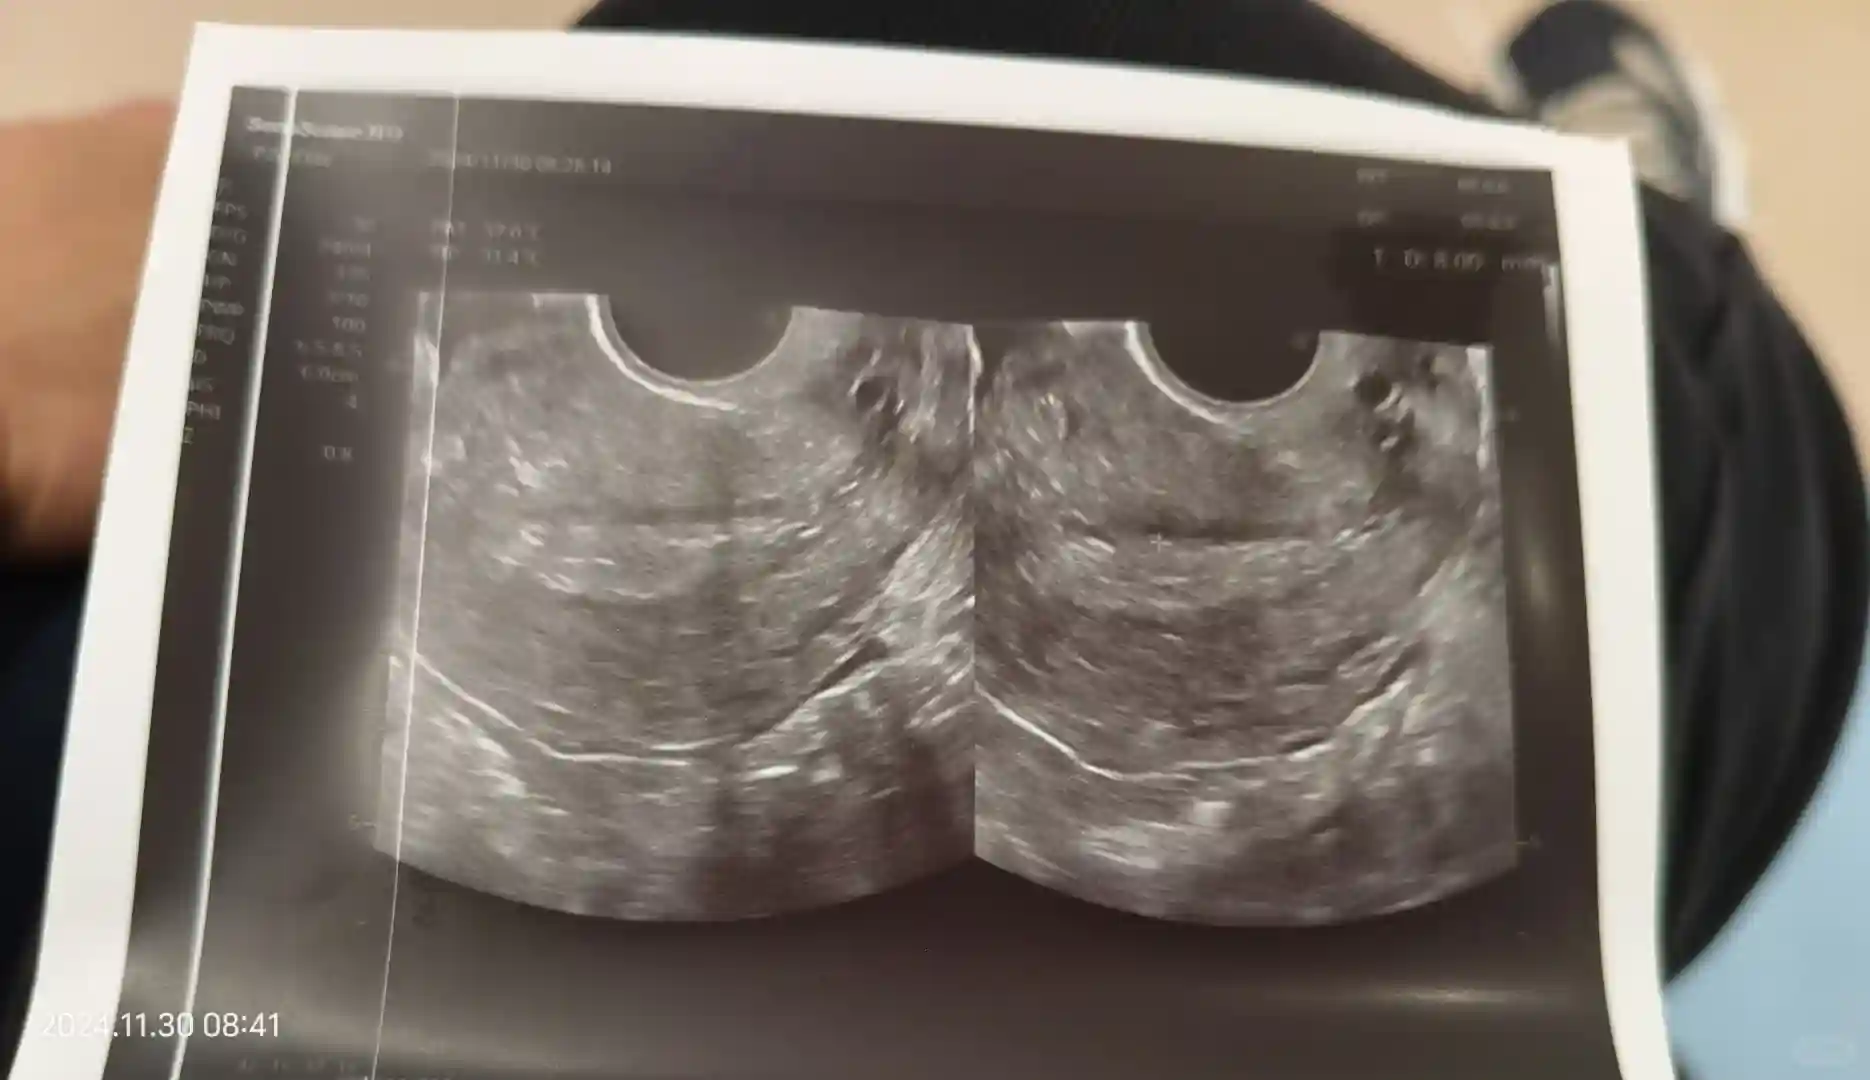

去四楼签字报道解冻移植。正好12点移植完成,这次移植老二和老三。一个4bc和一个4cb。

6号抽血,hcg27。成功着床。希望我的宝贝可以一切顺利,平安降生。